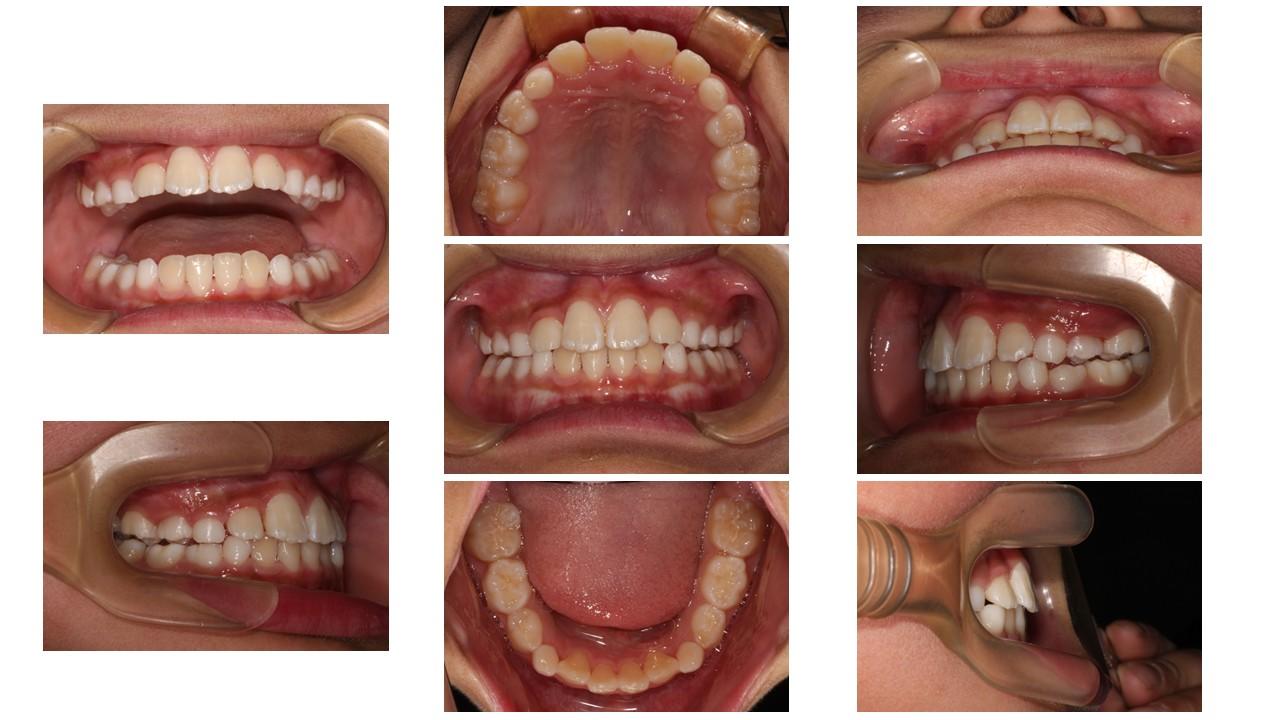

「叢生」は、一般的に「乱ぐい歯(らんぐいば)」「八重歯(やえば)」「ガタガタの歯並び」などと呼ばれる状態で、日本人に非常によく見られる不正咬合(ふせいこうごう:良くない噛み合わせ)です。

<叢生の状態>

顎(あご)の骨の大きさに対して、歯のサイズが大きすぎたり、歯が並ぶスペースが不足していたりするために、歯がデコボコに重なり合って生えている状態を指します。